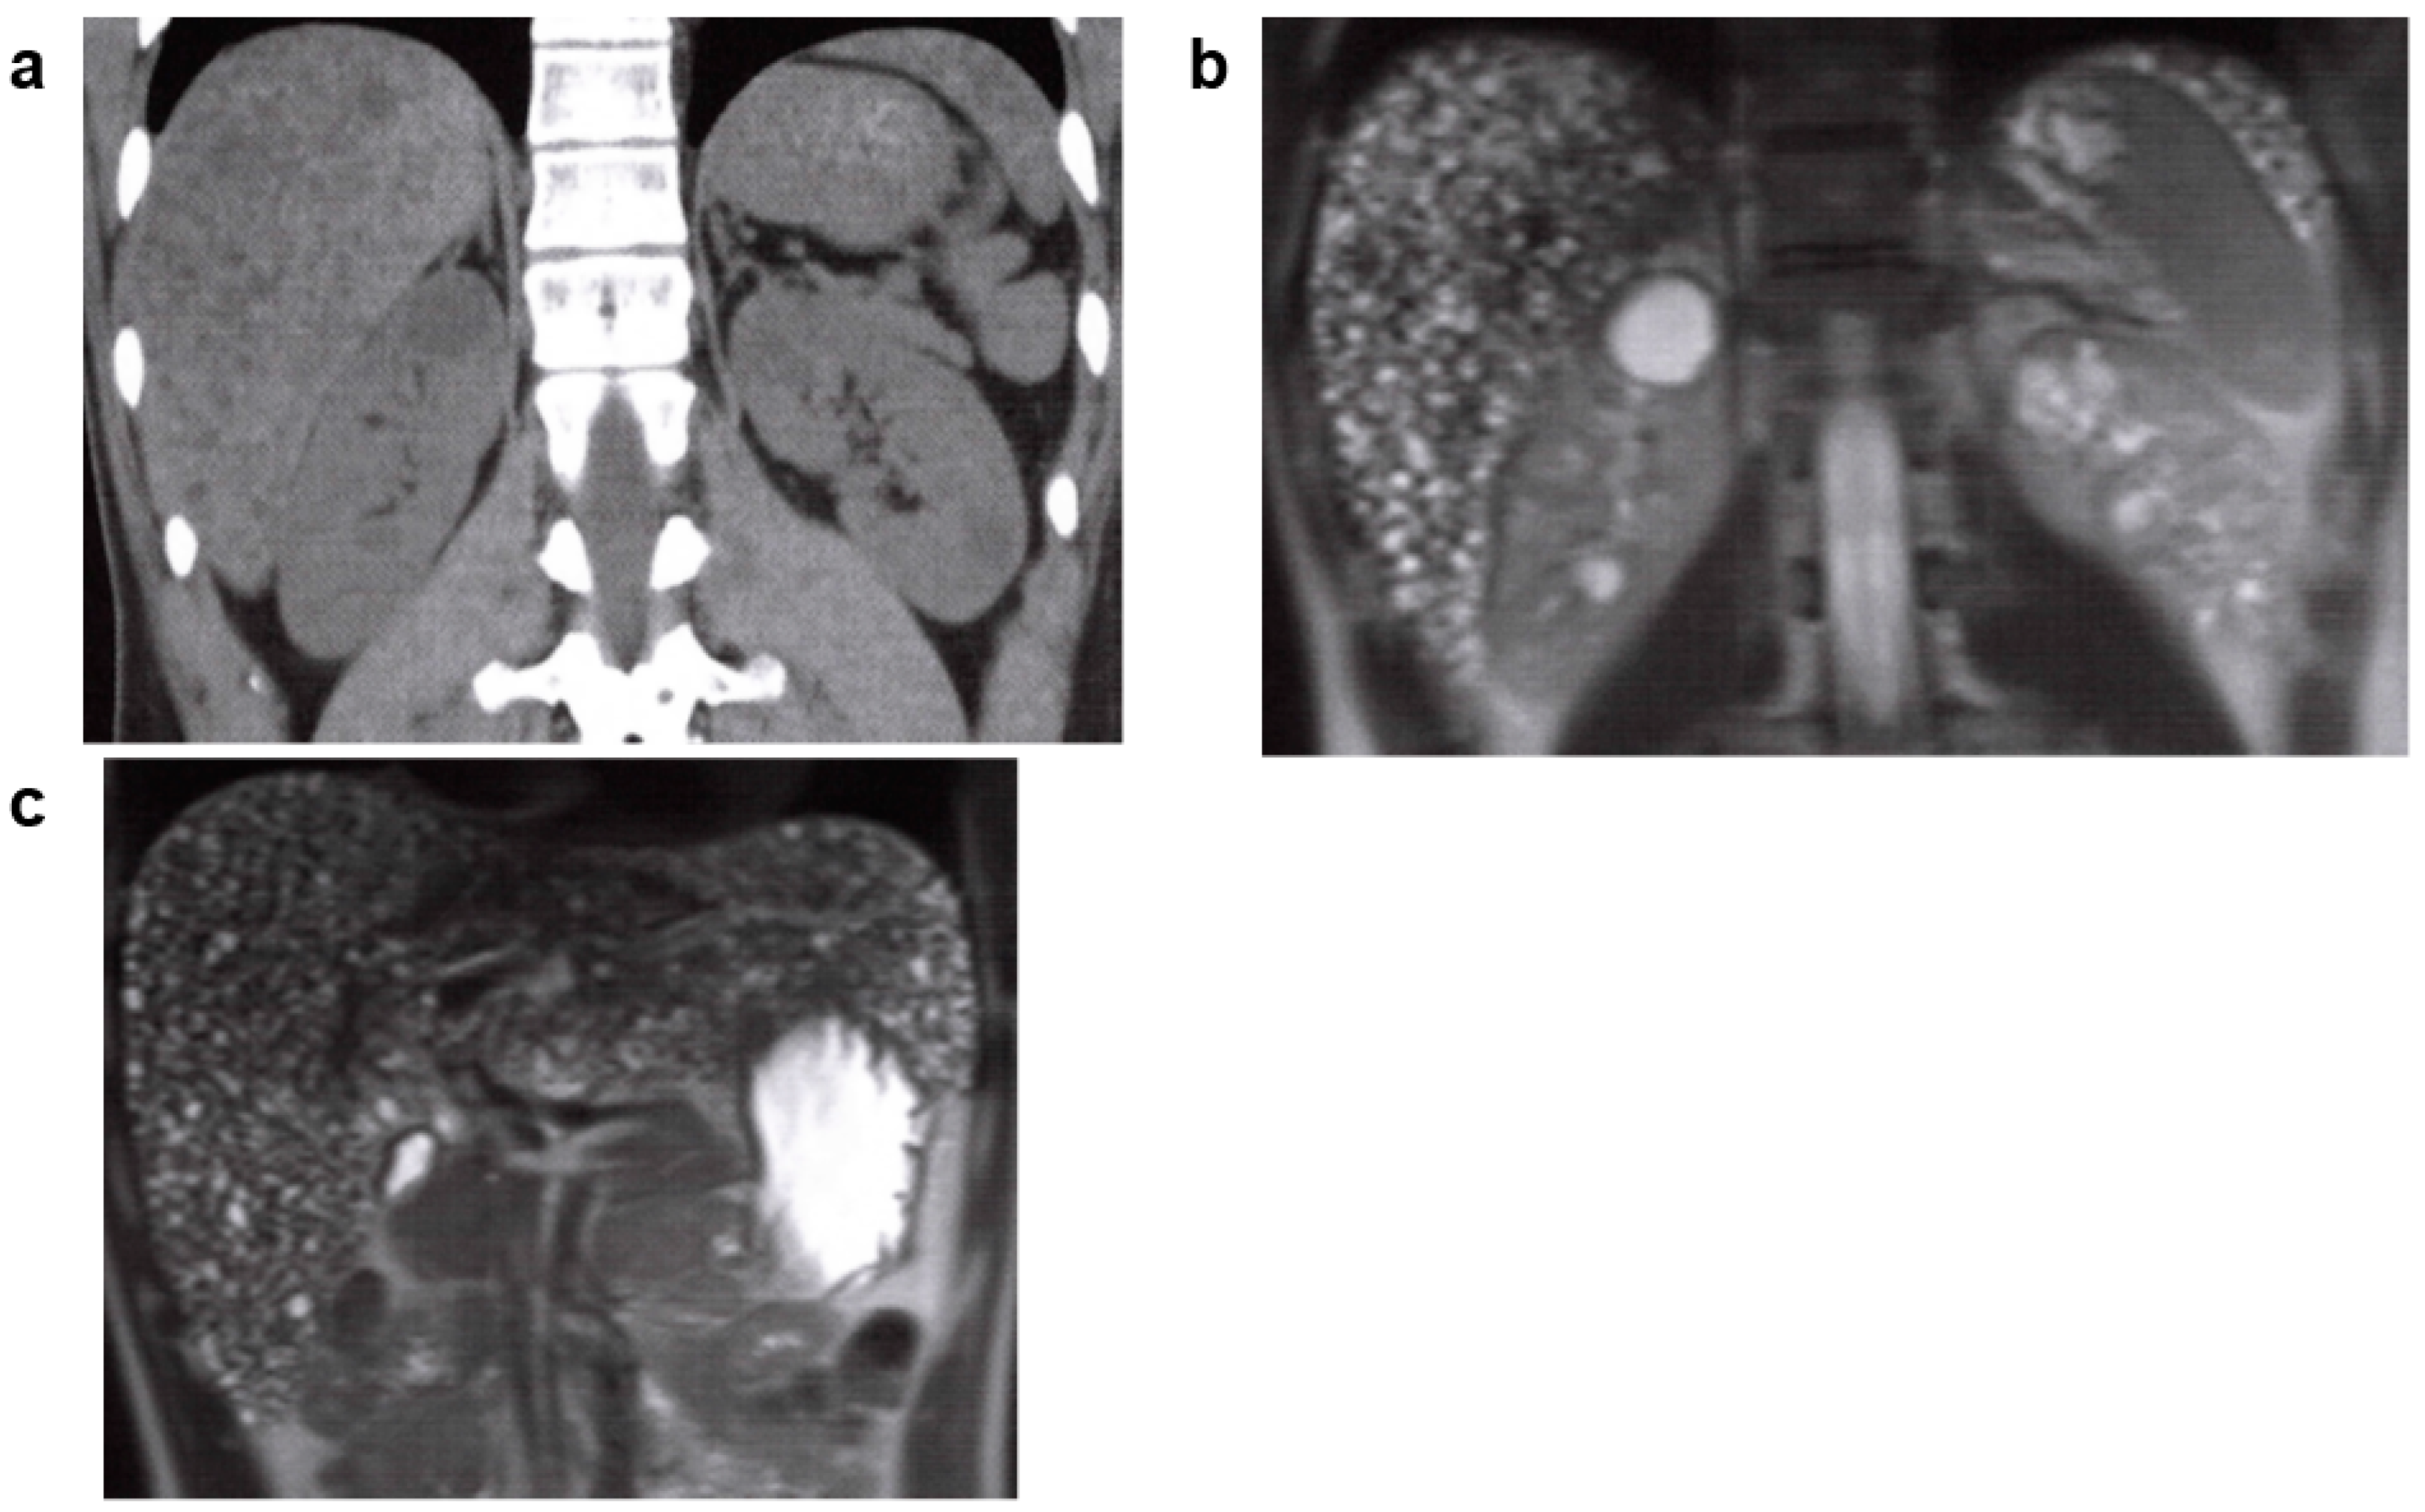

3.6.1. Tuberous Sclerosis (TSC)

3.6.2. Von Hippel-Lindau (VHL) Syndrome